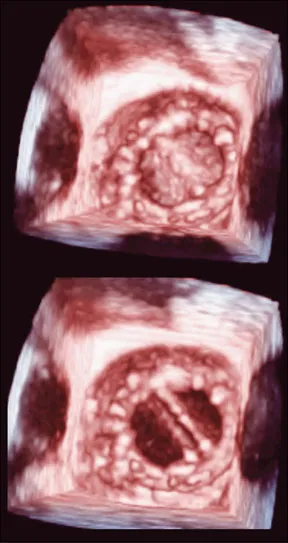

3-D Imaging Improves Diagnosis and Treatment of Valve Disease

Three-dimensional transesophageal echocardiography helps with surgical planning.

Cardiologists and cardiac surgeons are excited about a new technology that helps surgeons plan valve repair or replacement. Three-dimensional transesophageal echocardiography (3-D TEE) enables them to see the mitral valve and other heart structures in exquisite detail. "The technology provides images weve never seen before. With 3-D TEE, it is possible to better diagnose mitral valve disease or understand its pathology," says Cleveland Clinic cardiologist Takahiro Shiota, MD, an international expert on 3-D TEE and editor and author of the worlds first modern textbook on the subject of 3D echocardiography. Dr. Shiota says the new technology is so intuitive that even patients can understand it. "Most patients who see these realistic images are very impressed and express appreciation that they can better understand their mitral valve abnormalities," he says. The mitral valve is an ideal target for TEE, because it lies close to the esophagus. Patients swallow a probe tipped by a tiny ultrasound transponder, putting it within millimeters of the valve. Harmless, painless sound waves from the transponder are bounced off the valve, gathered by a computer and reconstructed into images on the screen.